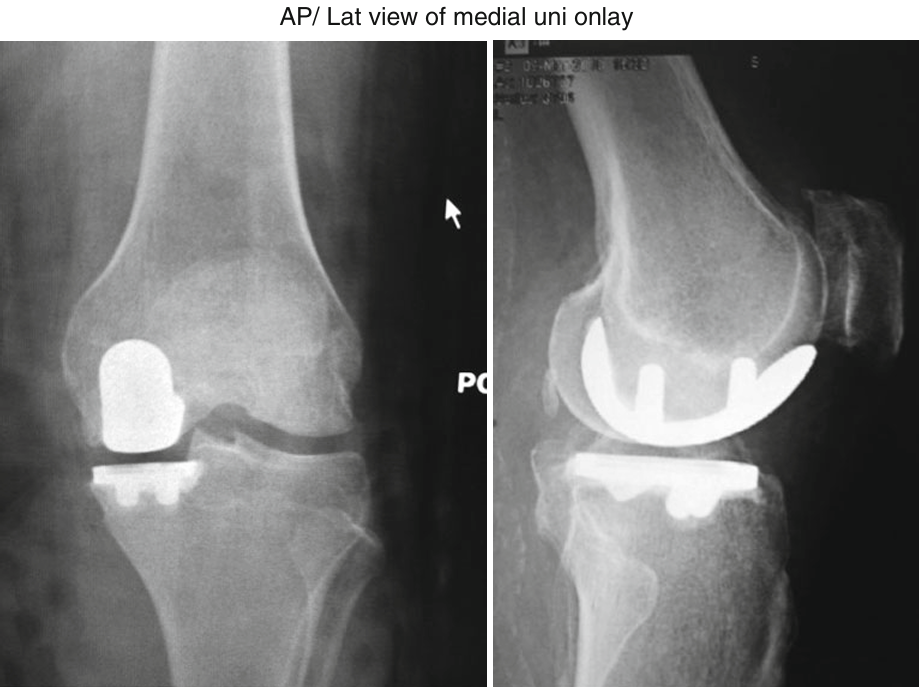

인공관절분야에서는 Partial Knee Replacement(PKR)인 Unicompartmental knee Arthroplasty(UKA)를 먼저 시행하다가 Total Knee Arthroplasty(TKA)로 로봇 수술은 넘어오게 되었습니다. 사실 로봇이 의사를 도와주는 역할을 하는 것이기 때문에 robotic-arm assistance for UKA (RAUKA) 이라고 부르는 게 더 맞을 것 같습니다. TKA에서도 좋지만 UKA 에서 이러한 로봇을 사용하는 것은 엄청난 장점을 가져오는 것 같습니다.